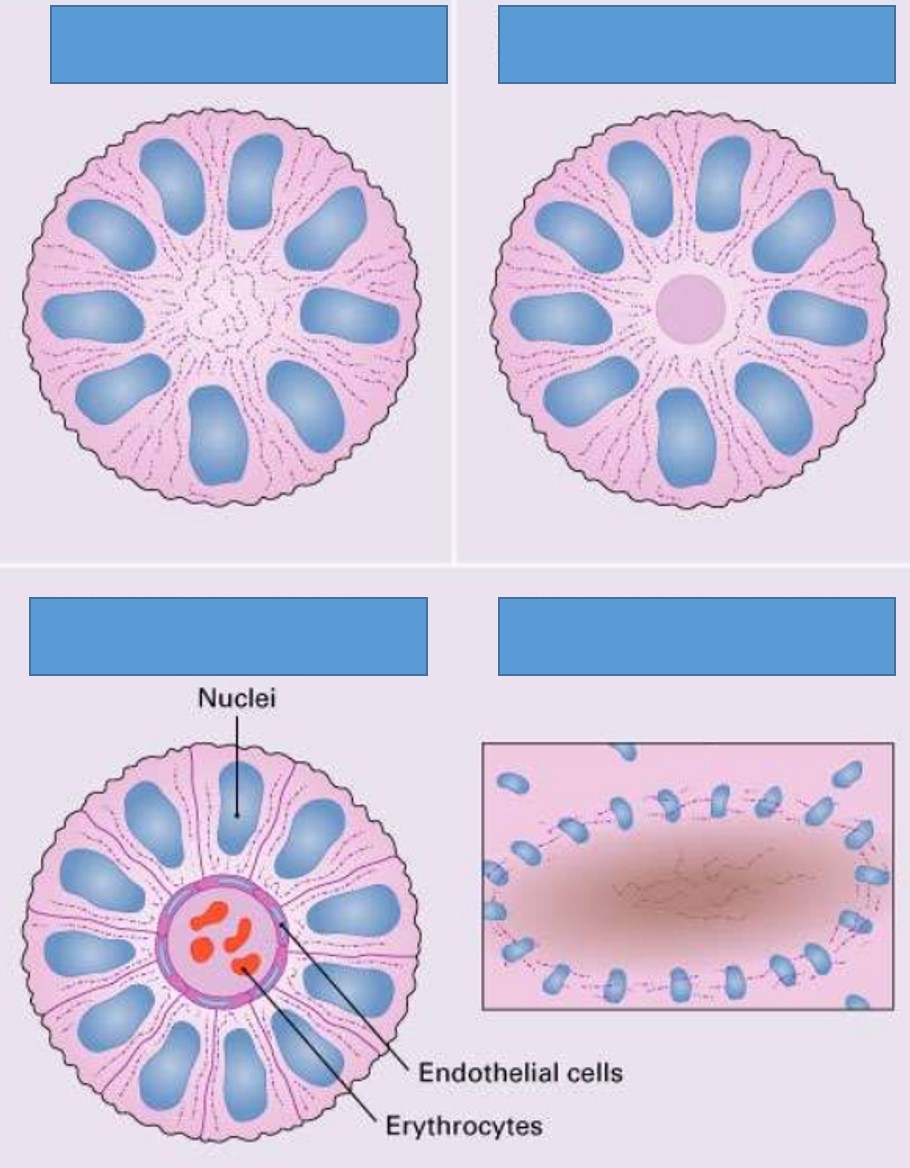

Oligodendroglioma

- 5-15% of gliomas

- Age: 40 ~ 50 y/o, rare in children

- Restricted to supratentorial compartment

- Interval to anaplastic progression is longer relative to astrocytoma (range 9y, vs 4-5y for latter)

- 1p, 19q deletion, oligodendroglial ‘signature’; connotes chemosensitivity

Ependymoma

- Incidence: 5% to 10% of primary brain tumors in the 1st two decades

- Arise around ventricular lining

- Locations:

- The 4th ventrical: common in children

- Spinal: adults, mean 40 yrs, NF2

- Loss/mutation of NF2 on chromosome 22q in spinal cord tumors